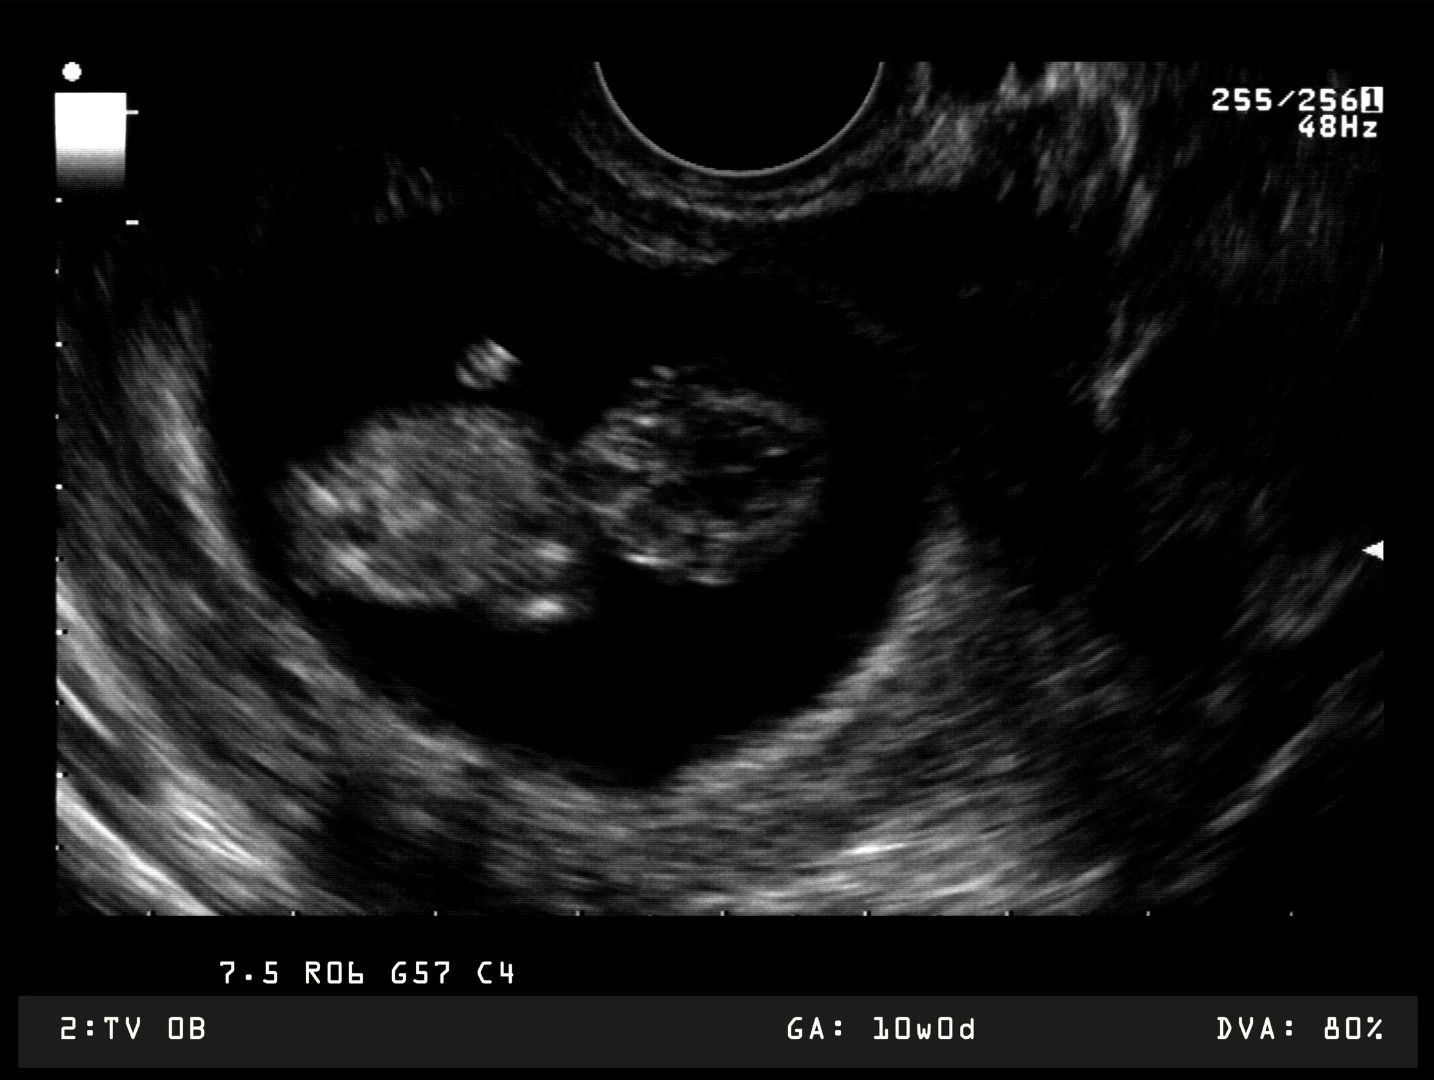

Đến với tuần thai thứ 12, cơ thể bé đã tương đối phát triển cứng cáp. Vì thế mà giai đoạn này cũng được xem là “thời điểm vàng” để mẹ kiểm tra nguy cơ mắc dị tật bẩm sinh ngay từ khi em bé còn trong bụng mẹ. Một số loại xét nghiệm mà mẹ thường được khuyến nghị làm bao gồm:

- Siêu âm đo độ mờ da gáy. Độ mờ da gáy là khoảng tích tụ dịch dưới da, ở vùng sau gáy thai nhi. Đối với những thai nhi mắc hội chứng Down và một số hội chứng bất thường nhiễm sắc thể khác, lượng chất lỏng này có thể tăng cao hơn so với các thai nhi khỏe mạnh. Xét nghiệm này thường được làm ở tuần thai thứ 11 - 14.

Đến với tuần thai thứ 12, mẹ nên bắt đầu làm một số xét nghiệm sàng lọc dị tật bẩm sinh cho bé.